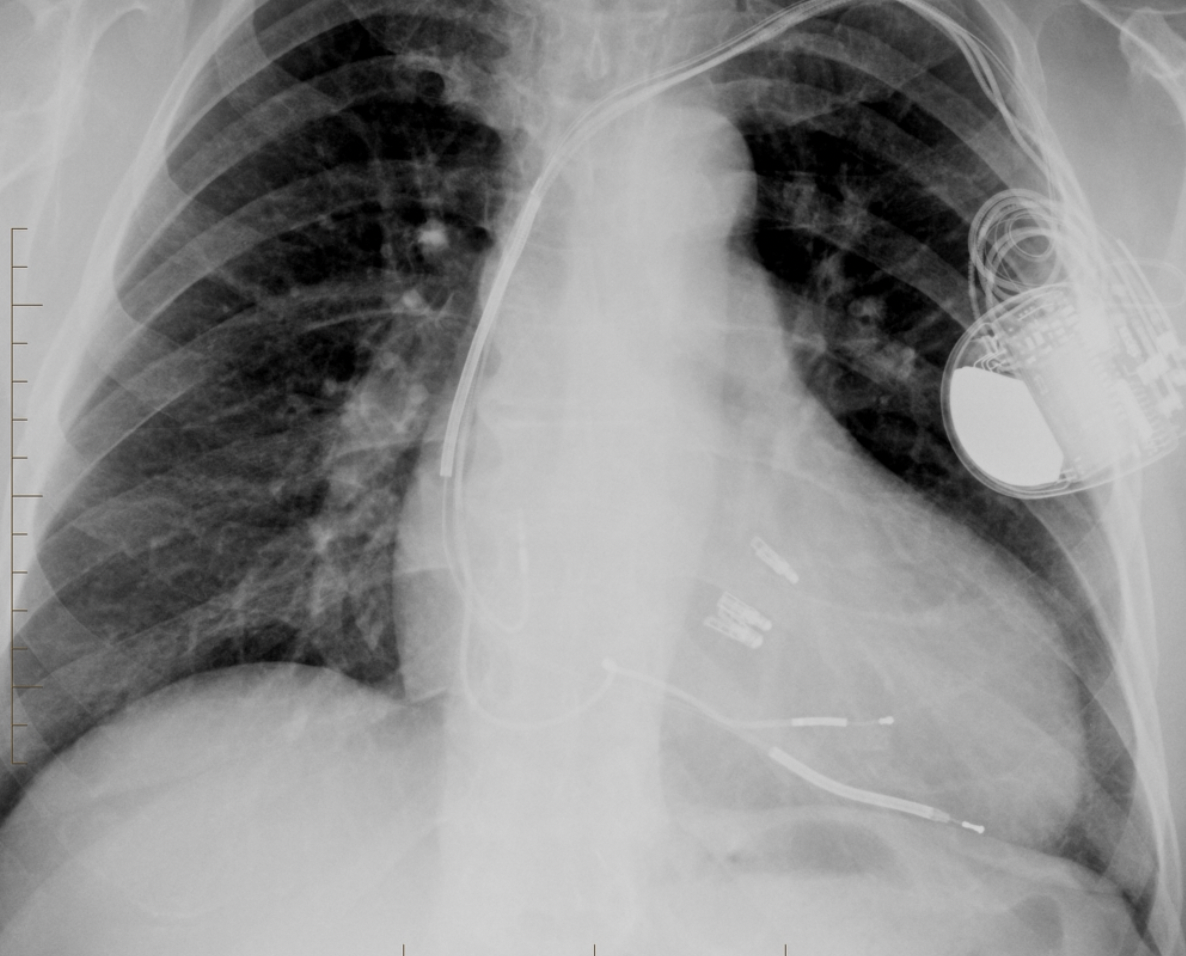

Atrial lead fracture (right by box), right pleural effusion,

How well did you know this?